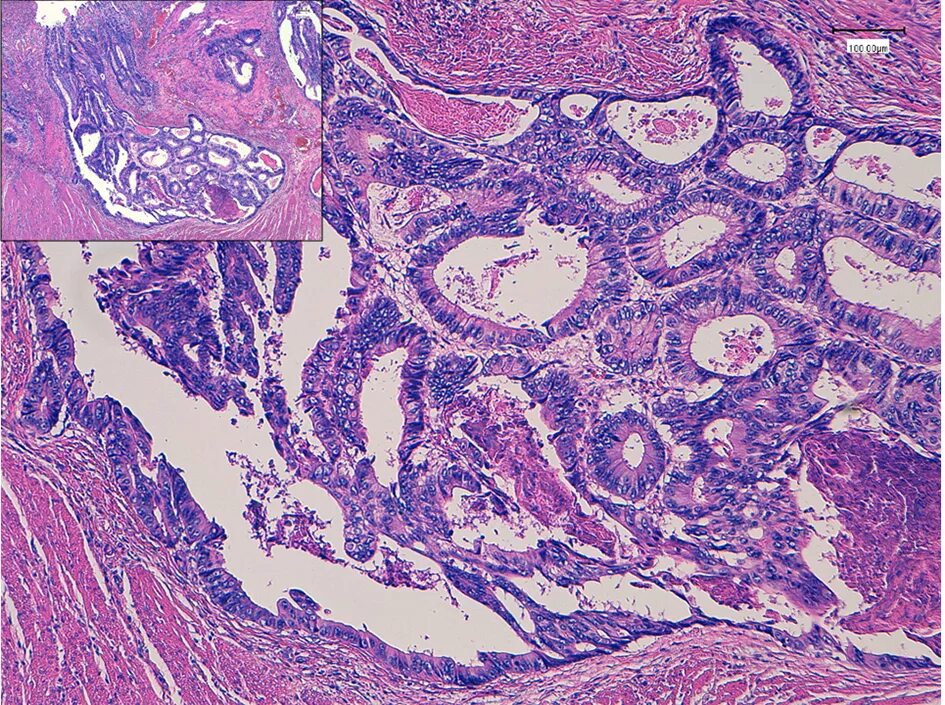

Гистология аденокарциномы